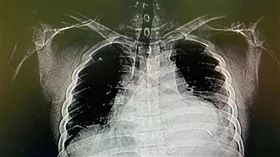

老婦腦部藏針80年!X光一照驚揭恐怖秘密

俄羅斯庫頁島(Sakhalin)一名80歲婦人到醫院...

悚!男嬰體內藏16根針 母:不知情

一名11個月大的男嬰體內,赫然發現被插入16根針,詭...

2018/01/24 12:04